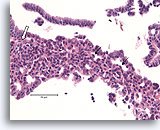

Papilloom, Borst FNA, Celblok.

Deze afbeelding van dezelfde FNA als in afbeelding 18 bevat een duidelijk papillaire architectuur.

10X

Papilloom, Borst FNA, Celblok.

Deze afbeelding van dezelfde FNA als in afbeelding 18 bevat een duidelijk papillaire architectuur.

10X